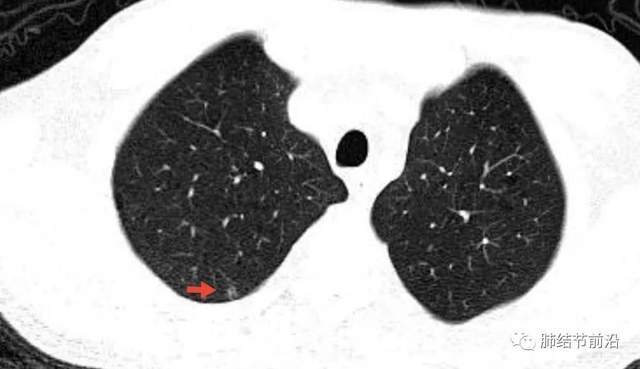

5mm的微小实性结节竟是恶性程度最高的肺癌

图片尺寸640x369